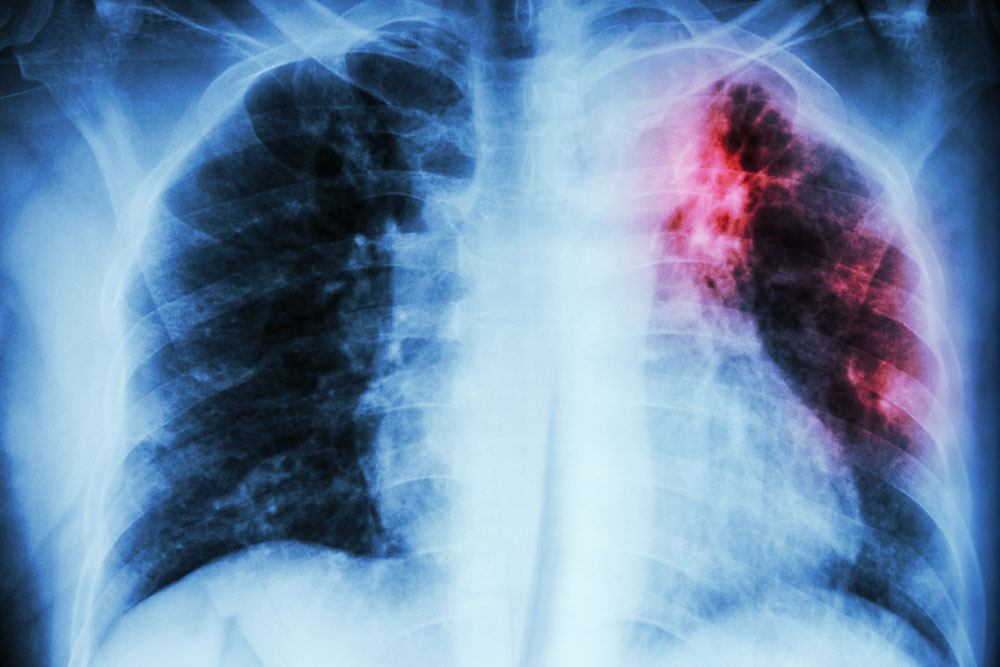

It is an ultrasound test for the heart. - Chest X-ray

This non-invasive technique provides a clear and detailed picture of your heart and lungs which the doctor can examine to detect any problem. - Computerized Tomographic Angiography